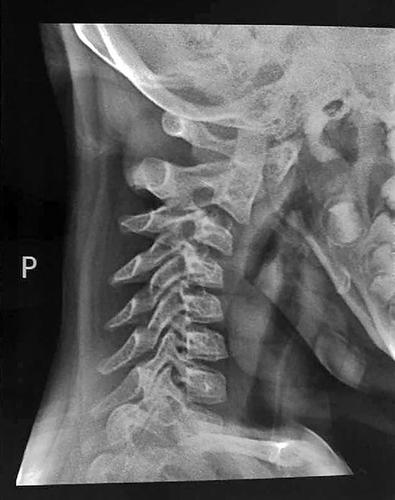

经过拍片检查,盈盈的颈椎第一、二、三椎向前错位。

“当时那个女孩的头颈向一侧扭转,稍微活动头部就直喊疼?!庇σ缴?,经过拍片检查,盈盈的颈椎第一、二、三椎向前错位,“这么严重的颈椎病发生在这么小的孩子身上,这是我从医30多年来头一回碰到?!?/p>